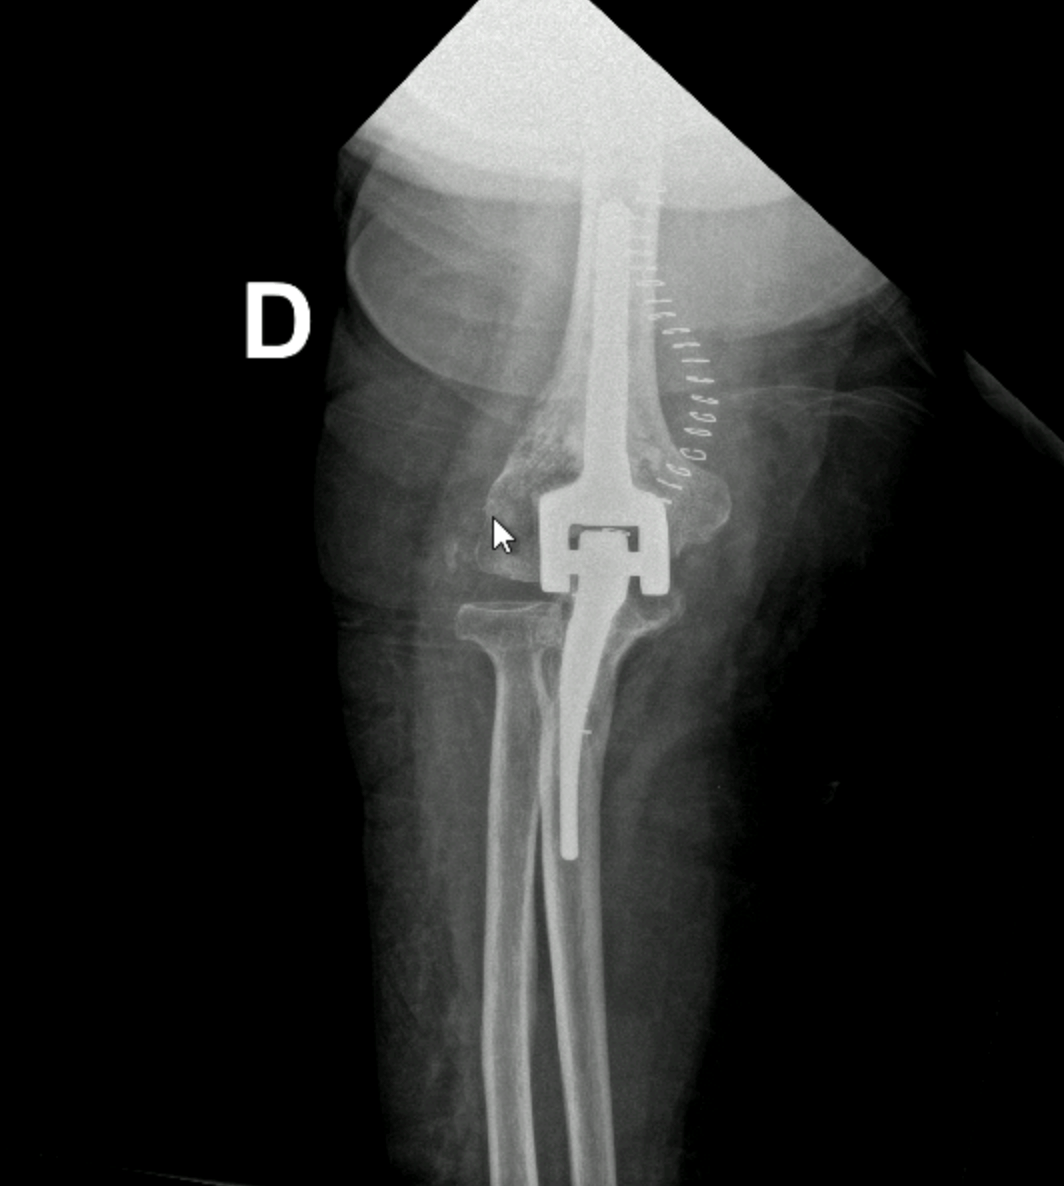

La prothèse remplace tout ou partie de l’articulation du coude par des composants artificiels, le plus souvent en métal et en polyéthylène.

Il existe plusieurs types de prothèses selon la pathologie et l’état des ligaments :

- Prothèses totales liées (les plus fréquentes)

- Prothèses non liées

- Prothèses partielles